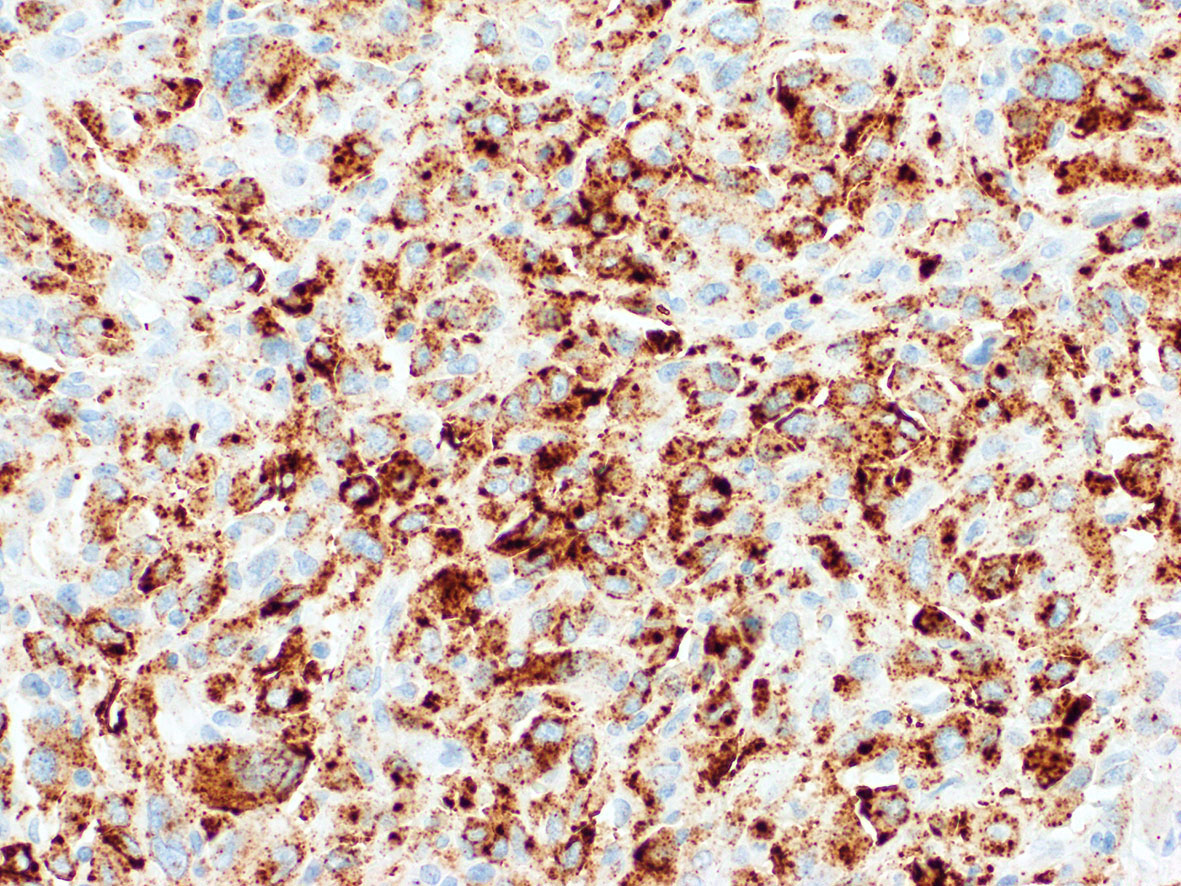

Microscopic (histologic) images

Contributed by A. Cristina Vargas, M.B.B.S., Ph.D., Patricia Guzman, M.D., Fiona Bonar, M.B.B.Ch., Alison Cheah, M.B.B.S. and Martin Jones, M.B.B.S.

Positive staining - disease

- ALK overexpression as a result of gene translocations / fusions:

- ALK+ anaplastic large cell lymphoma (ALCL) (Science 1994;263:1281, Semin Diagn Pathol 2020;37:57)